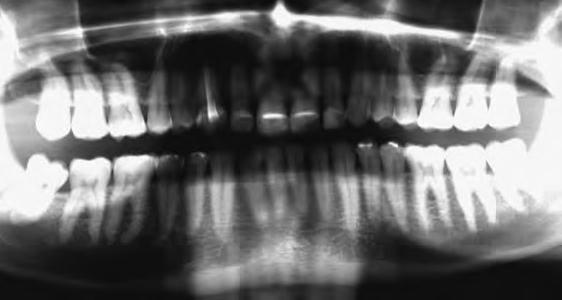

Dr. Miguel Stanley, dr. Ana Gomes Paz, dr. Inês Miguel (Portugália) Dr. Christian Coachman (Brazília) 1. ábra: Kiindulási állapot (frontális irányból). 2. ábra: A kiindulási állapotról okkluzális irányból készített felvétel (felső állcsont). 3. ábra: A kiindulási állapotról okkluzális irányból készített felvétel (alsó állcsont). 4. ábra: A kiindulási állapotról készült panorámaröntgen felvétel (2015).

2015-ben egy 47 éves férfi páciens állkapocs-ízületi panaszai miatt kereste fel a rendelőnket. Ezen felül esztétikai problémát jelentett számára, hogy az egyik felső nagymetszőfogán lévő héj eltört (1-3. ábrák). A klinikai és radiológiai vizsgálatot követően megállapítható volt, hogy a páciens kifejezett bruxizmusa miatt csökkent a harapási magassága, és jelentős mennyiségű saját foganyagot abradált el (4. ábra)

15. ábra: A végleges pótlások átadása után készült panorámaröntgen felvétel.